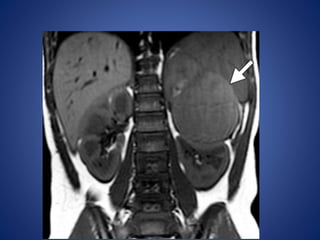

At MR imaging, the solid portion of the tumor demonstrates intermediate signal

intensity with multiple hyperintense cystic spaces on T2-weighted images,

creating a spongelike appearance

At MR imaging,the solid portion of the tumor demonstrates intermediate signal intensity with multiple hyperintense cystic spaces on T2-weighted images, creating a spongelike appearance